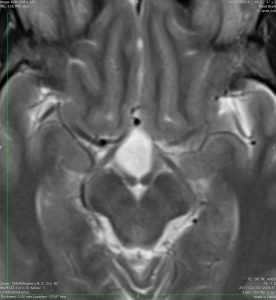

思春期の女の子にできた小脳腫瘍です。とても大きく見えますがほとんどが水たまり(のう胞といいます)。第4脳室が腫瘍で圧迫されて閉塞性水頭症になりました。のう胞の中に出血がありますが毛様細胞性星細胞腫では腫瘍内出血をしばしば見ます。右の写真で脳室が大きくなっています。こんなに大きいのに小脳症状は全くなくて,頭痛と嘔吐が症状でした。

赤で塗ったところだけが毛様細胞性星細胞腫です。これを取れば治ります。簡単な手術ですし後遺症も残りません。

手術後のMRIです。水頭症も改善してますから症状も消失しましたし,すぐに退院です o(^o^)o